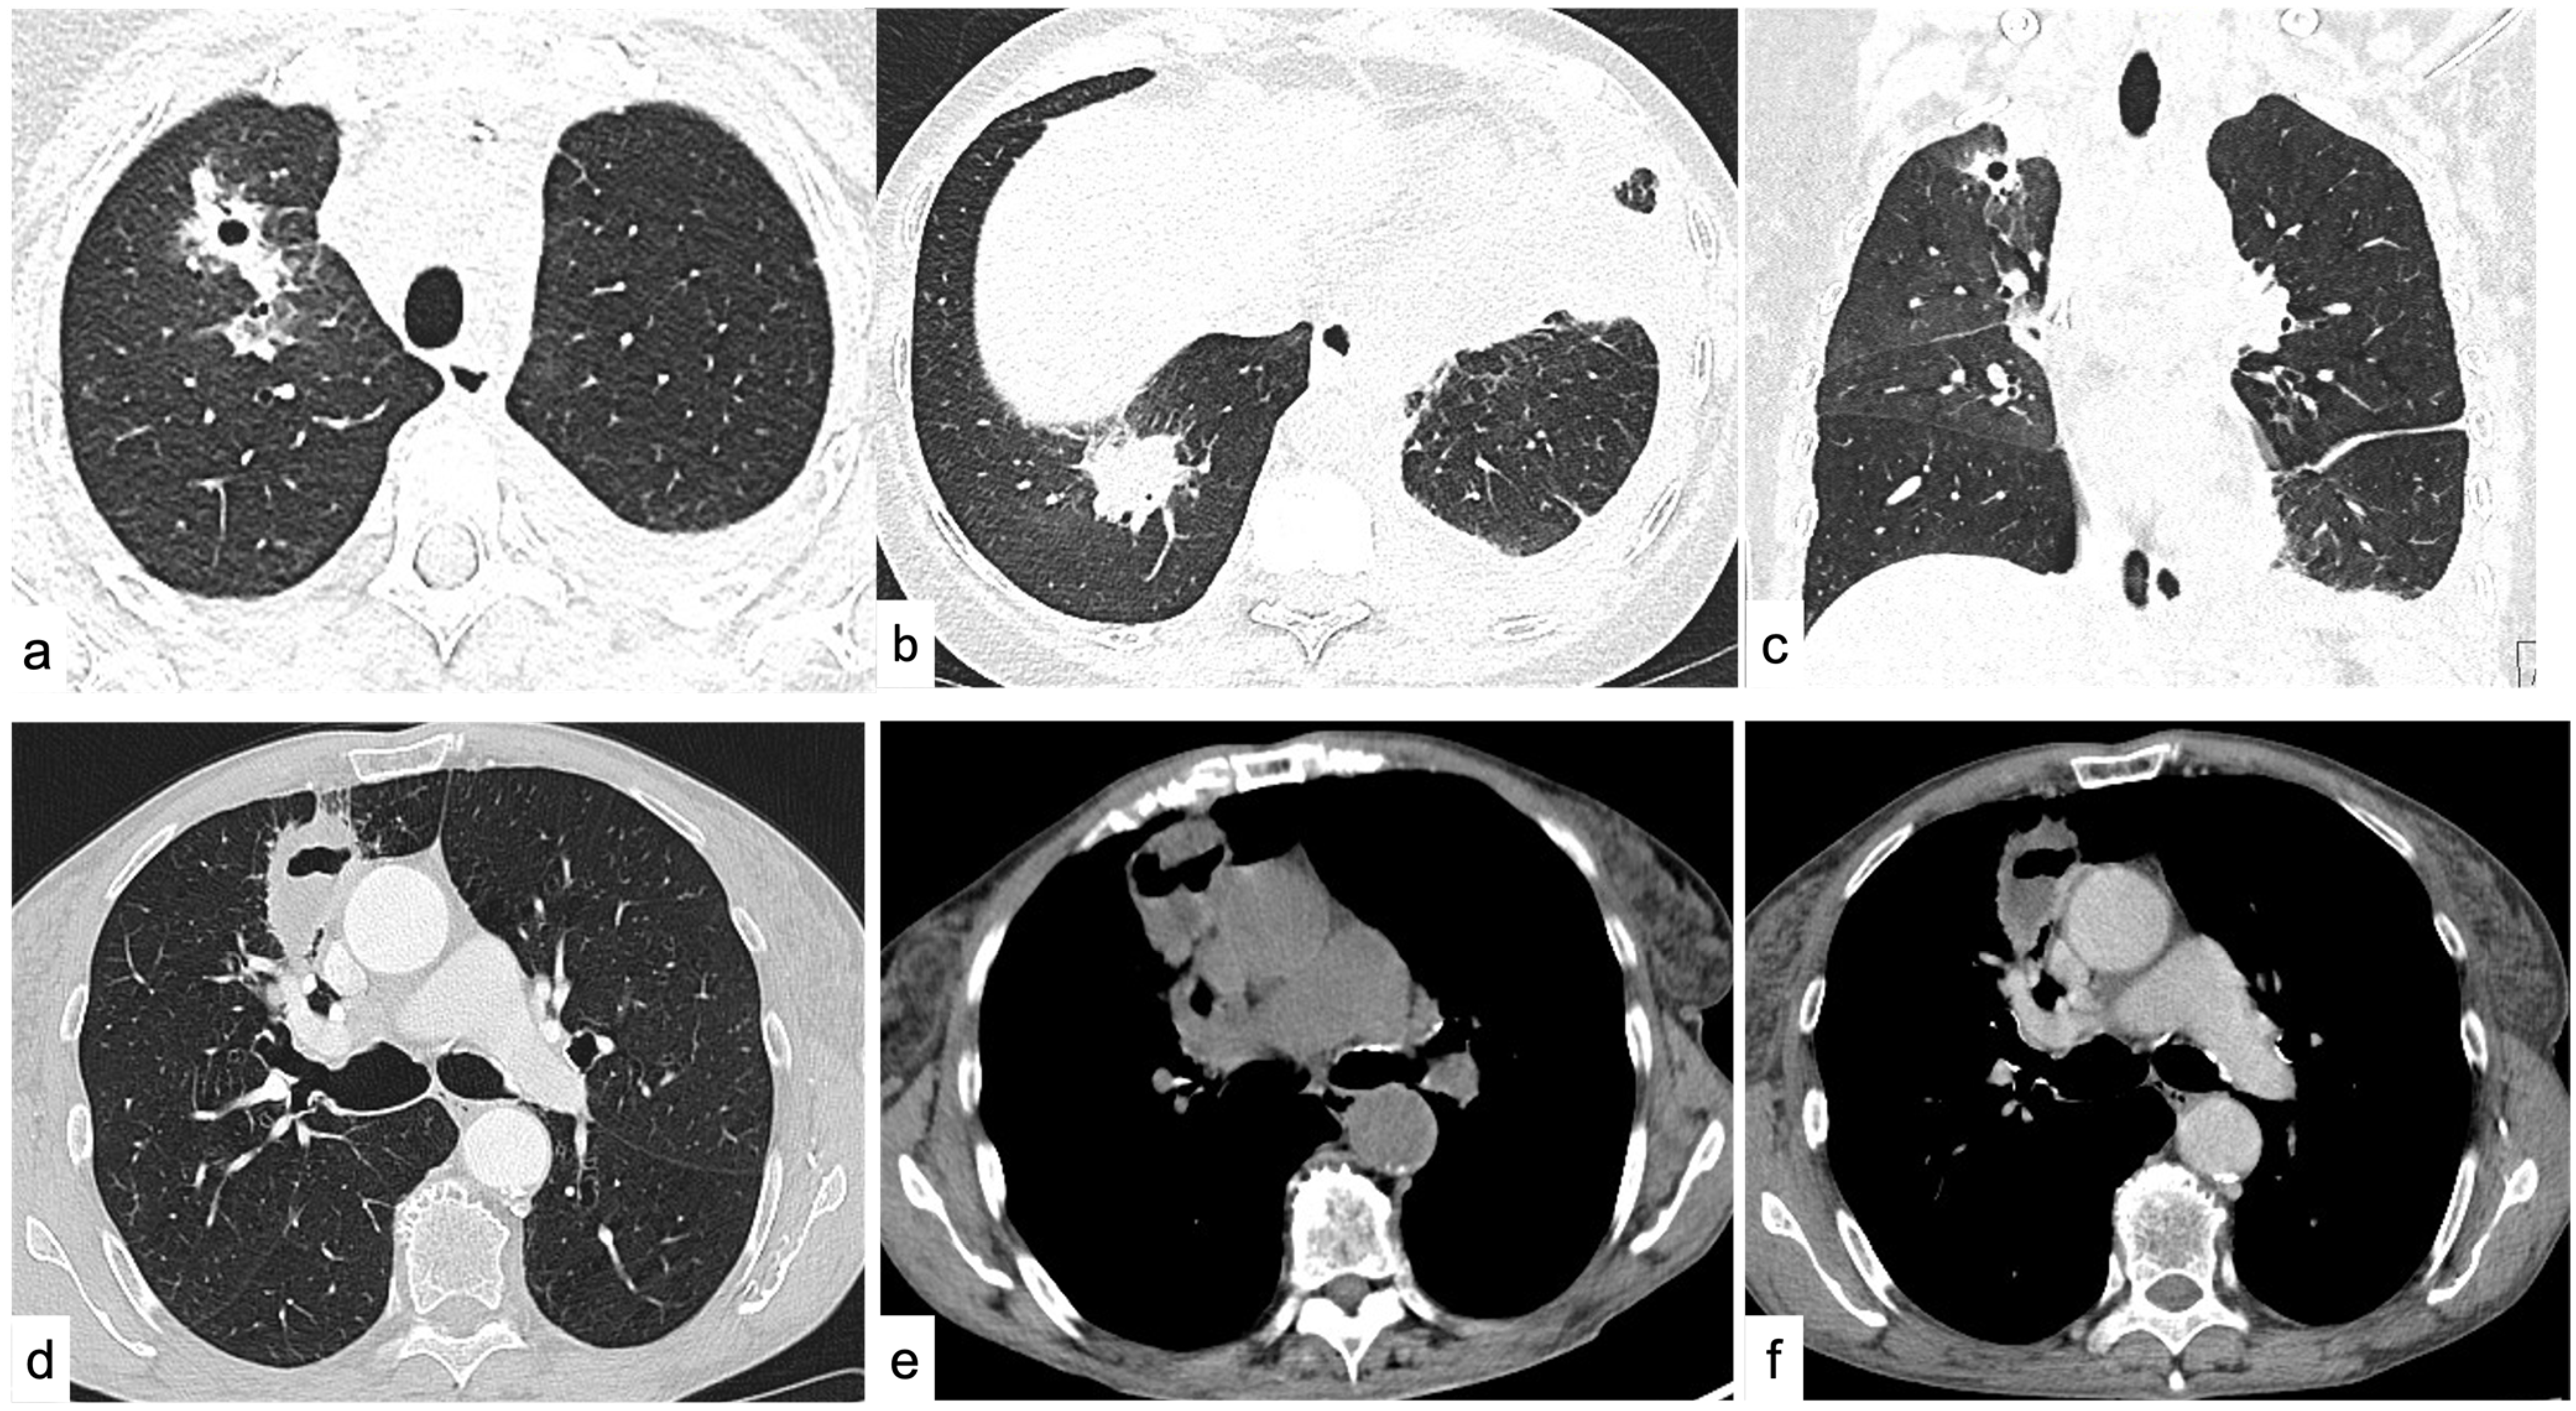

4.1.6. Cavitations and Cysts

4.2. Diffuse Lung Disease